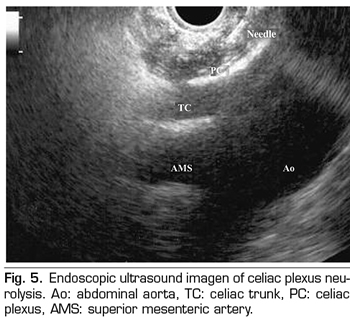

ENDOSCOPIC ULTRASOUND NEUROLYSIS OF THE CELIAC PLEXUS

Endoscopic ultrasound offers the advantage of larger visualization of the celiac plexus at a short proximity, allowing larger precision and safety in the administration of the neurolytic agent and avoiding injection into vascular structures through the use of Doppler (37) (Figure 5). However, the studies supporting endoscopic ultrasound neurolysis, considered similarly to percutaneous technique as a rescue therapy, are limited to retrospective uncontrolled studies (38). Pauli et al. published a meta-analysis that concludes that this technique achieves an 80% pain reduction in patients with pancreatic cancer (39). Some studies show a slight decrease in opioid consumption, but without strong scientific evidence.